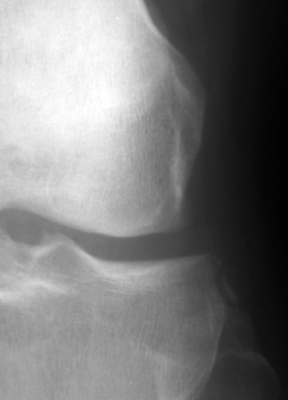

Frontal radiographs of the knee which reveal a small fleck of bone adjacent to the lateral aspect of the lateral tibial plateau. This "lateral capsular sign" is a simple radiographic finding visible on the routine AP knee x-ray, which indicates severe lateral capsular injury and should alert the examiner to the possibility of ACL tear. The fleck of bone represents an avulsion of the meniscotibial portion of the middle one-third of the lateral capsular ligament. It most commonly implies a disruption of the capsular ligament and the ACL. A-B Radiographs. C. MRI confirms the diagnosis of ACL tear.

AP knee - Click on the image for a larger versionAAP knee - Click on the image for a larger versionB - Click on the image for a larger versionC